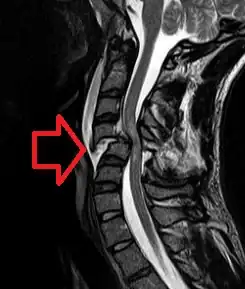

![]() | |

| MRI of a fractured and dislocated cervical vertebra (C4) in the neck that is compressing the spinal cord | |